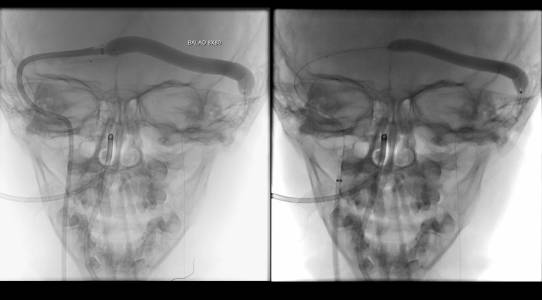

Foi realizada discussão entre as diversas especialidades, em vista da não melhora com o uso do anticoagulante, foi sugerido a tentativa de trombectomia mecânica do seio dural.

O caso clínico apresenta a utilização de materiais com finalidades primárias para trombectomia mecânica no contexto de acidente vascular cerebral (Rebar 27 + Solitaire) e o balão Copernic RC (Balt) comumente utilizado auxiliando na embolização de fístulas durais para os seios, auxiliando no processo de trombectomia mecânica no contexto de extensa trombose venosa cerebral.